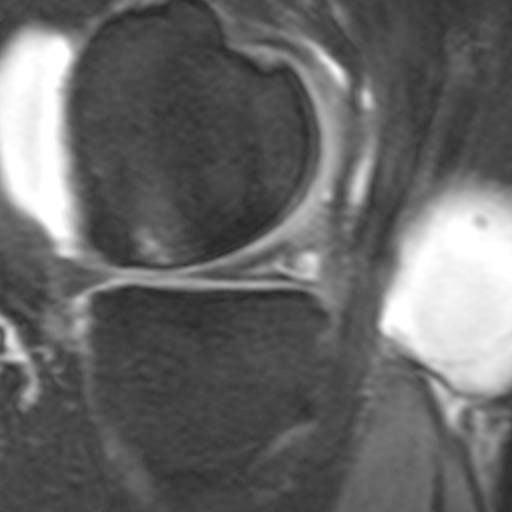

Typischer, grosser Meniskusriss im MRI (Magnetresonanztomographie)